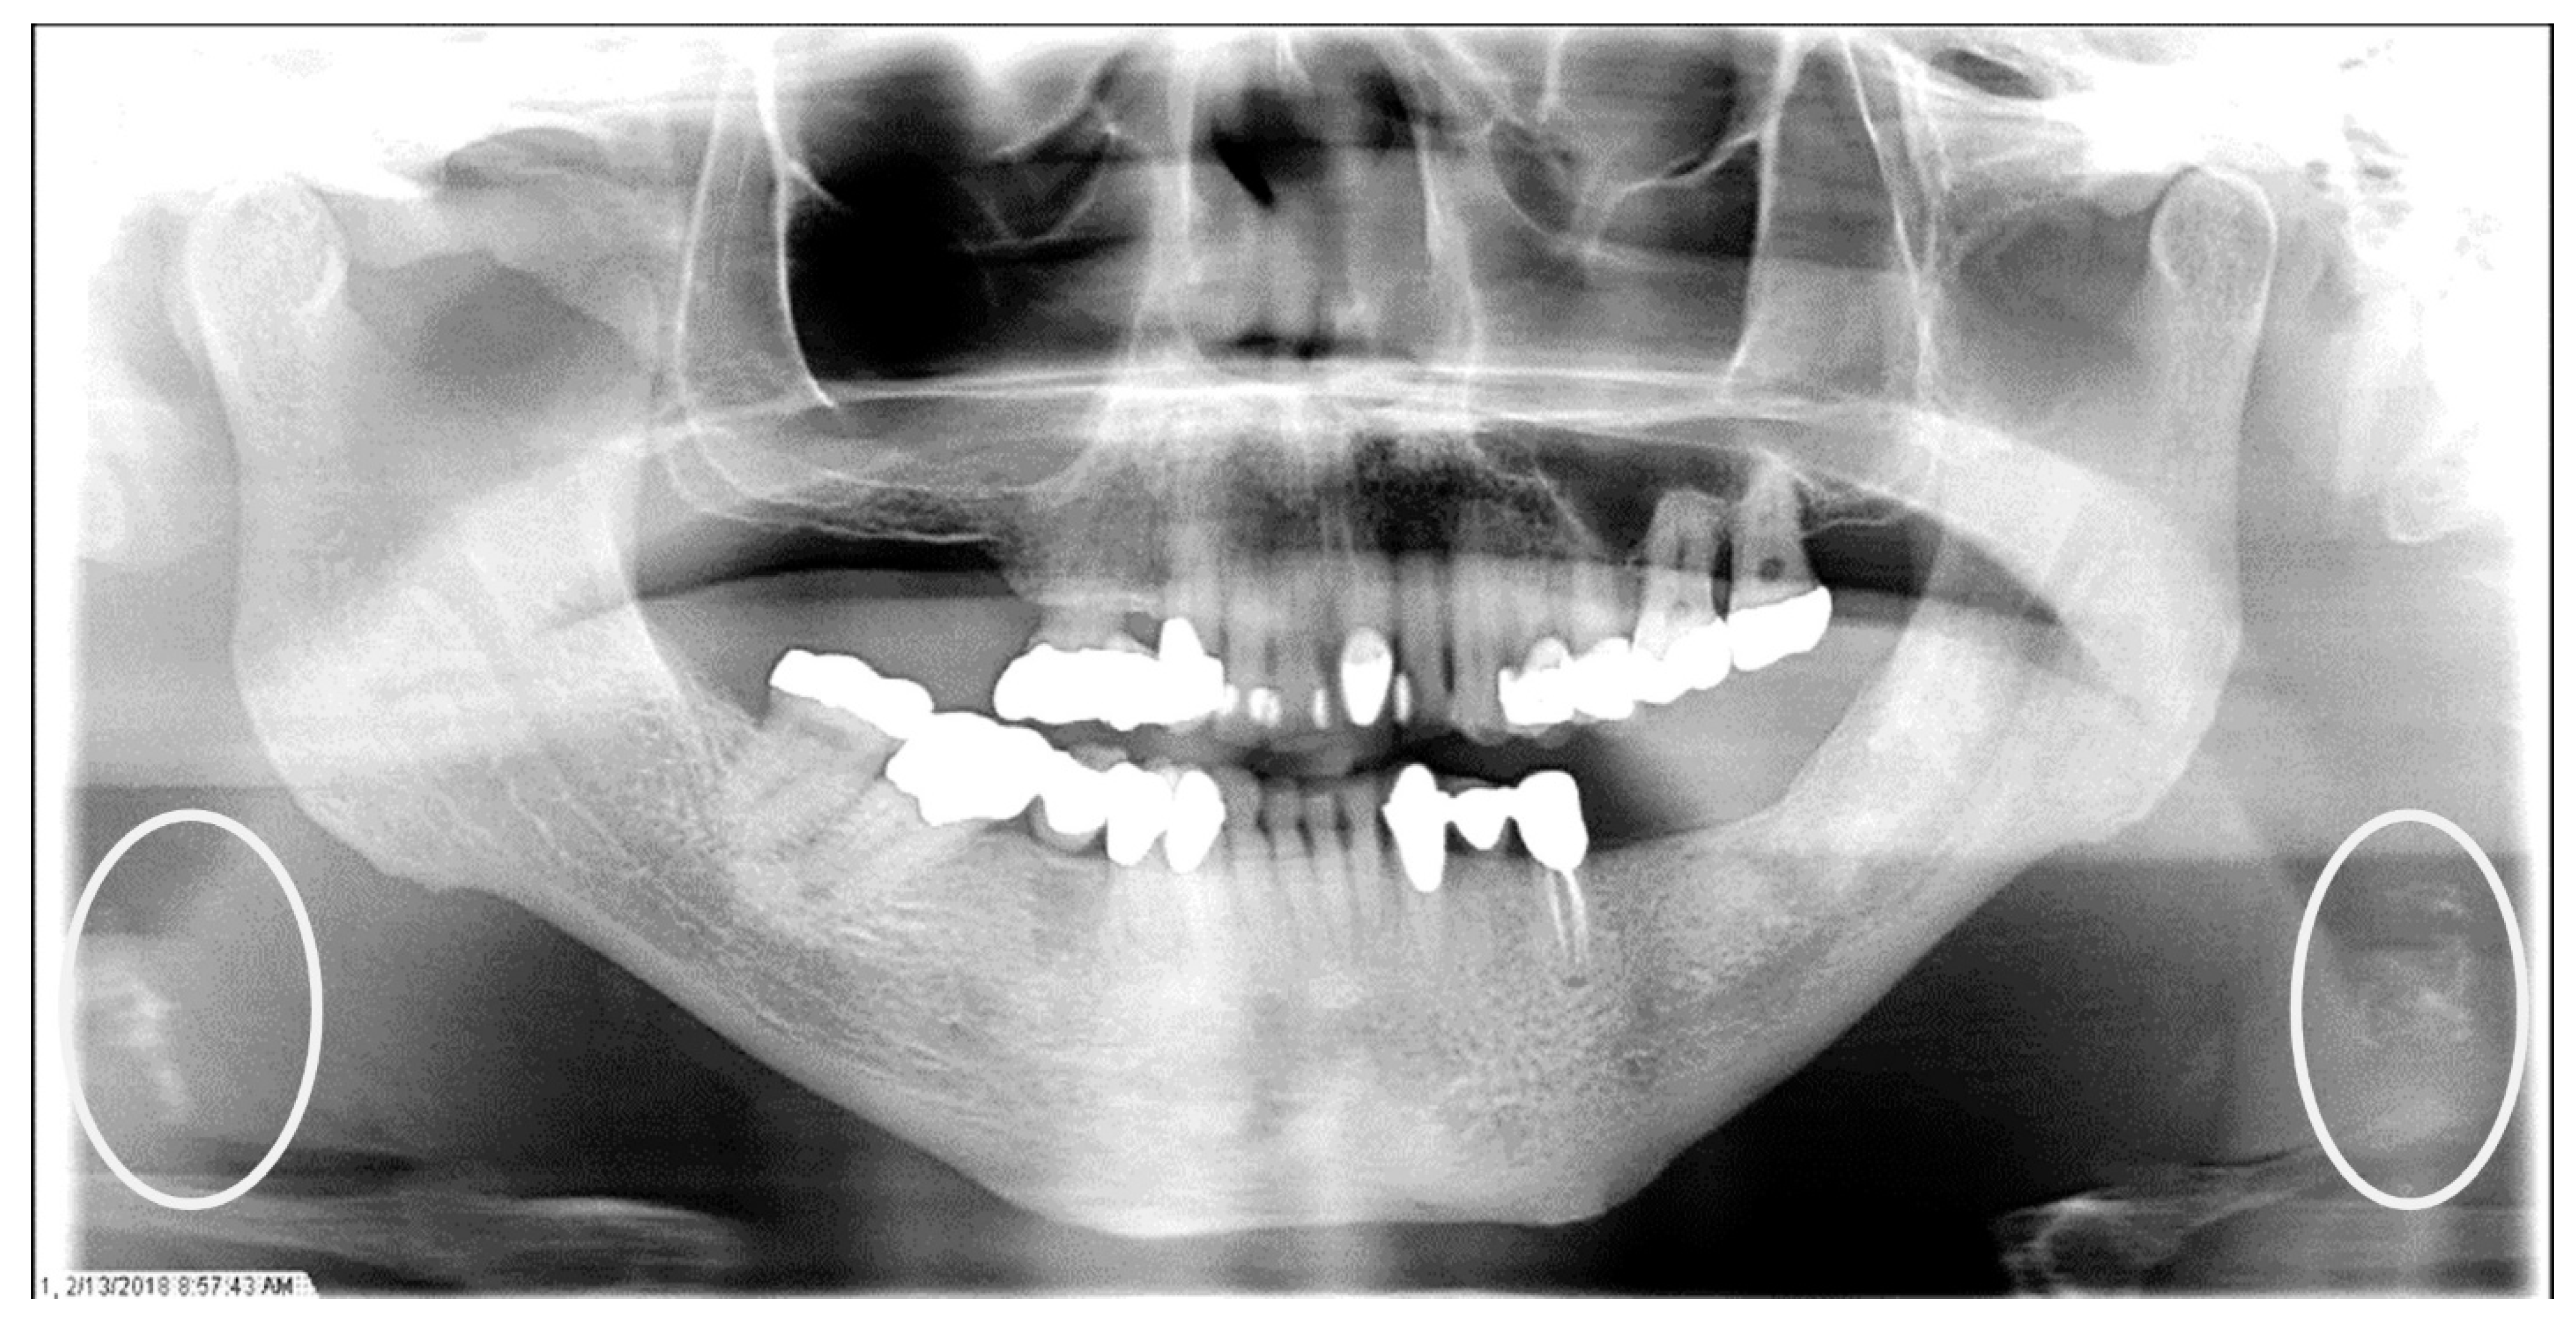

The characteristics of the CAC patients are presented in Table 1. Between 2014 and 2023, there were 559 patient records with the terms “carotid artery calcification” or “carotid” or “calcification of the carotid artery” noted. After the panoramic radiographs were reviewed, 314 patients were confirmed to have a diagnosis of CAC (including 26 patients with a history of carotid endarterectomy). The remaining 245 patient records were excluded because of the absence of detectable CAC on PRs and the absence of PRs to review. The ages ranged from 29 to 92 years, with a median of 68 years. CAC was most prevalent (39.5%) in the seventh decade of life. There were 168 (53.5%) female and 146 (46.5%) male patients. The median age of the female patients was 68 years, and the median age of the male patients was 69.5 years. The calcifications were identified unilaterally in 168 (53.5%) patients (88 females/80 males; mean age: 67.8 years) (Figure 1 and Figure 2) and bilaterally in 146 (46.5%) patients (80 females/66 males; mean age: 68.6 years) (Figure 3, Figure 4 and Figure 5). The DMFT index in the CAC patients ranged from 8 to 32 (mean = 26.6). The frequency of patients with CAC with a history of hypertension, hyperlipidemia, diabetes mellitus, CVA, and CAD was 86.2%, 57.6%, 30.7%, 15.5%, and 28.7%, respectively.

Figure 5.

The panoramic radiograph of a 53-year-old male patient with a medical history of hypertension and hyperlipidemia showing bilateral carotid artery calcifications (CACs) during a comprehensive dental examination. The CACs are encircled by a white line.